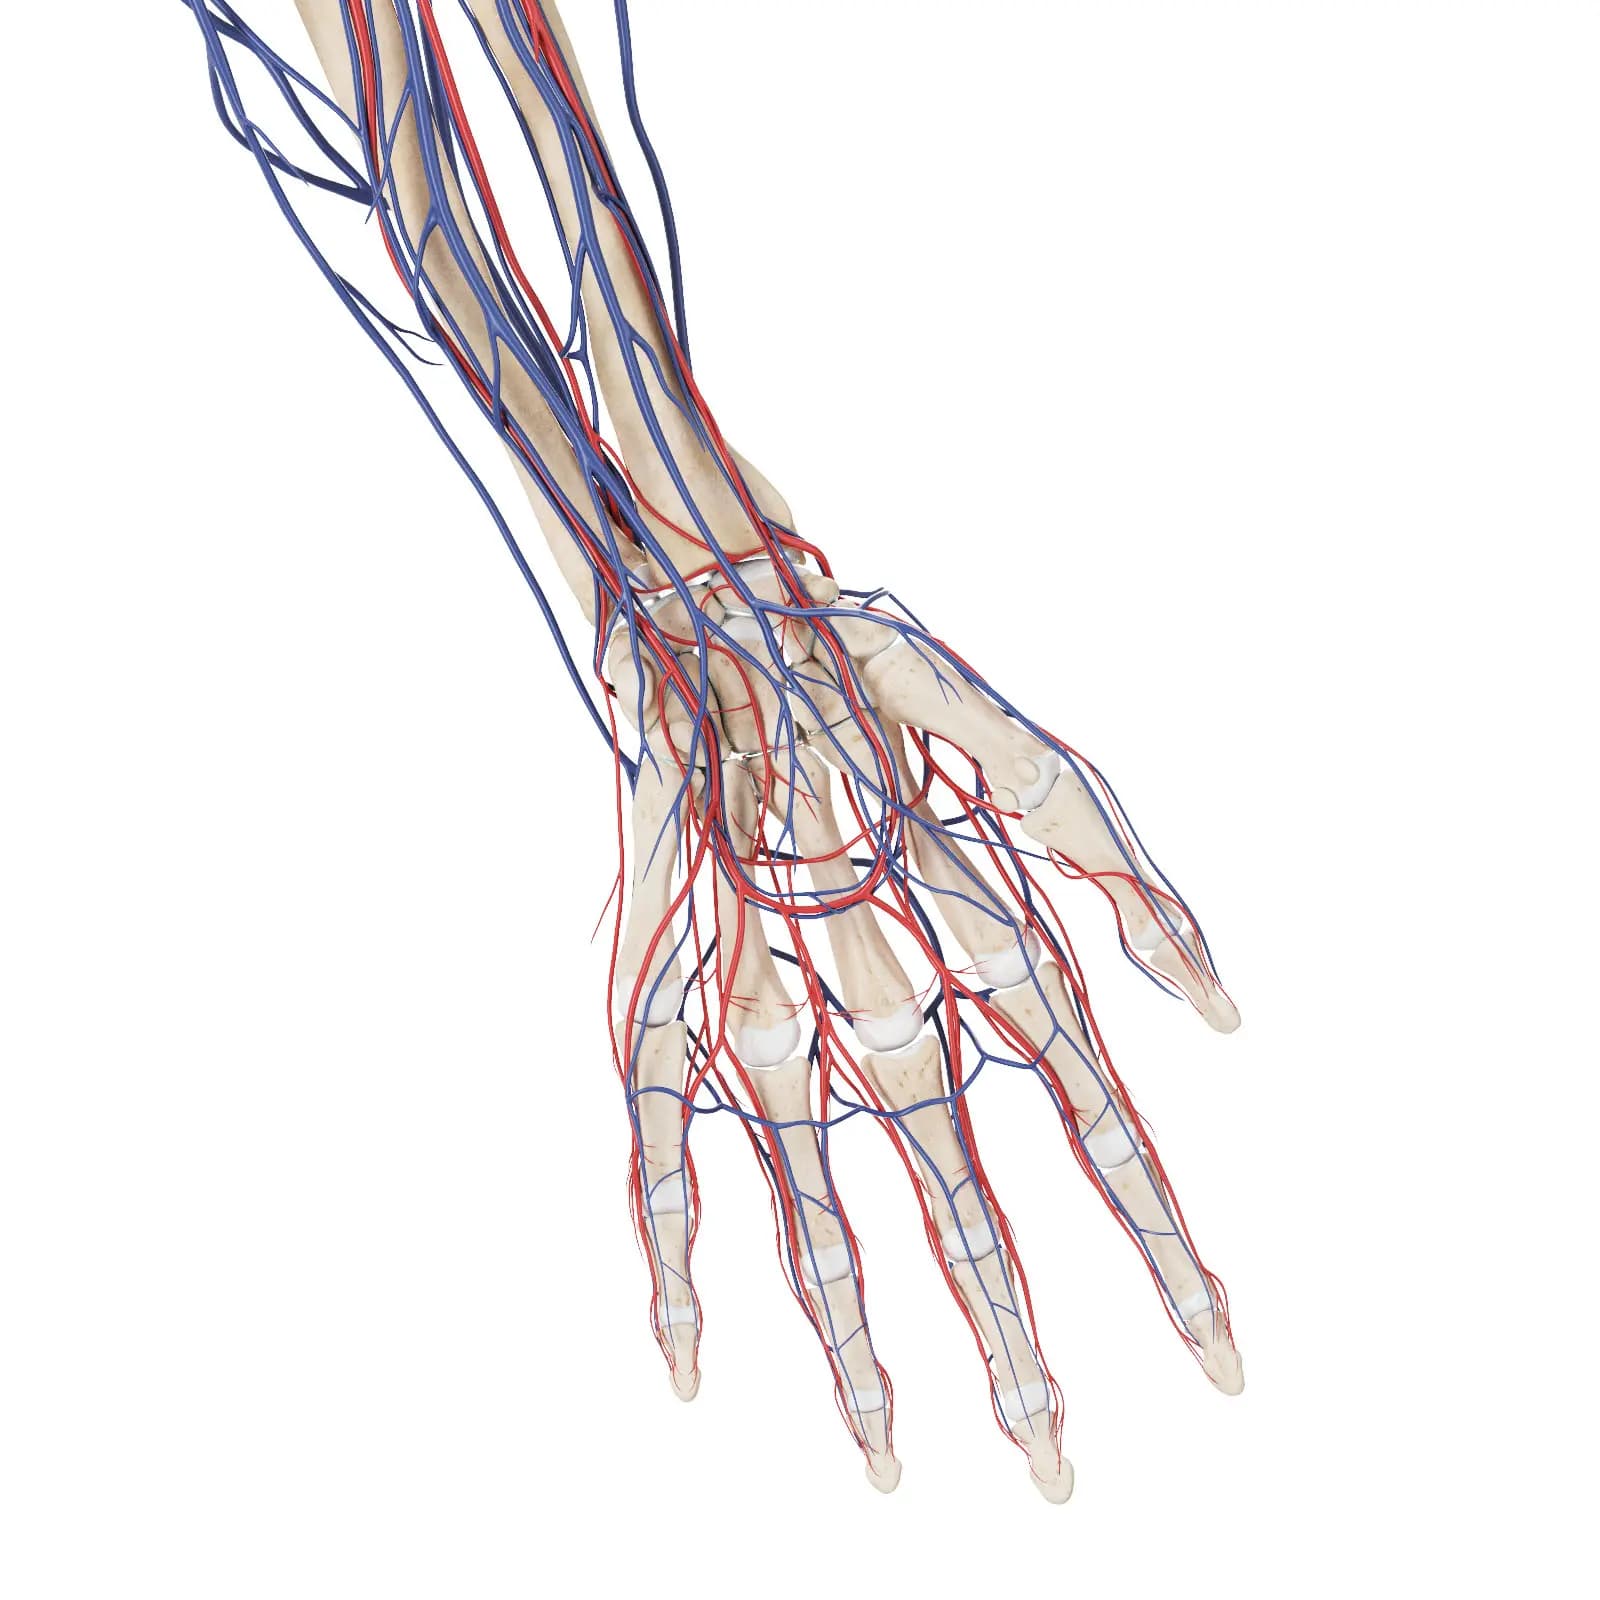

3d Rendered Medical Illustration Of The Vascular System Of The Hand